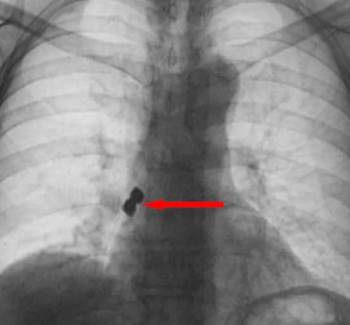

Afyonkarahisar’Da 56 Yaşındaki Bir Kadın Tedavi İçin Gittiği Diş Kliniğinde Yanlışlıkla 2 Adet İmplantı (Diş Kaplaması) Yuttu. Yuttuğu Dişler Akciğerine Kaçarak Sağ Nefes Borusunu Tıkayan 56 Yaşındaki Kadın Ölümden Döndü.

Afyonkarahisar’da 56 yaşındaki bir şahıs tedavi için gittiği diş kliniğinde yanlışlıkla 2 adet implantı (diş kaplaması) yuttu. Yuttuğu dişler akciğerine kaçarak sağ nefes borusunu tıkayan 56 yaşındaki şahıs ölümden döndü.

Olay Emirdağ ilçesinde meydana geldi. İddiaya göre, Belçika’nın Brüksel kentinde yaşayan 56 yaşındaki D.K., isimli gurbetçi vatandaş implant diş tedavisi için Emirdağ’daki bir kliniğe gitti. Operasyon esnasında birbirine yapışık halde olan 2 adet implant bir anda hastanın dişinden düştü. İmplantlar ardından hasta yutkununca akciğerlere kaçıp sağ nefes borusunu tıkadı. Nefes almakta zorlanan D.K., ardından Emirdağ Devlet Hastanesi’ne kaldırıldı. Burada yapılan müdahalenin ardından D.K., Afyonkarahisar kent merkezindeki bir hastaneye sevk edildi. Burada D.K.’nın akciğerine kaçan implantlar cerrahi operasyona gerek kalmadan, bronkoskopi yöntemi adı verilen tıbbi müdahale ile çıkarıldı. İmplant yüzünden ölüm tehlikesi atlatan D.K., birkaç gün hastanede kaldıktan sonra taburcu edildi.